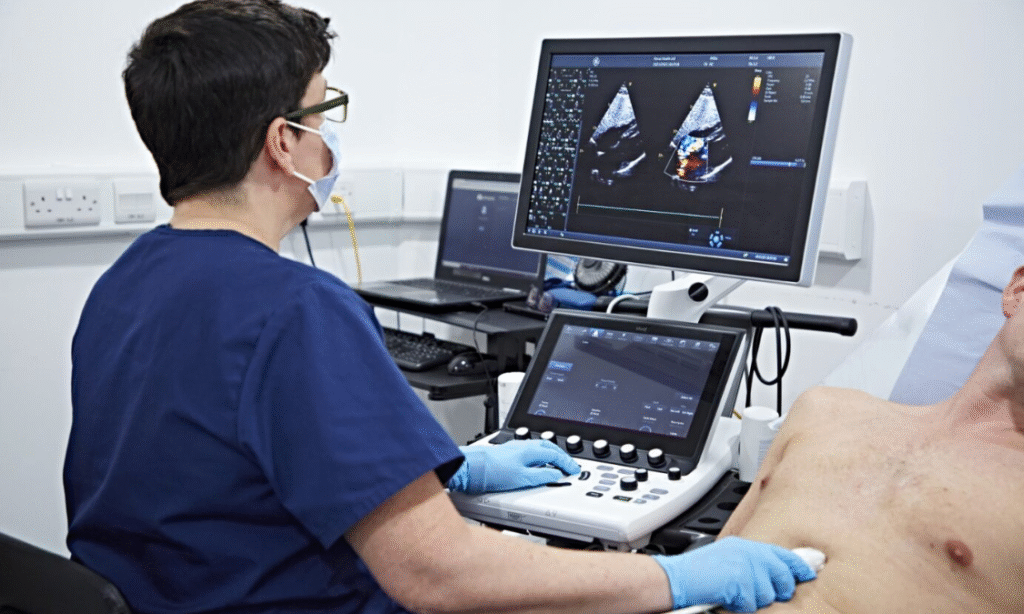

Cardiology – ECG & Echo

Non-invasive heart screenings with specialist review

We provide 12-lead resting ECG, 2D & 3D Echo, and Doppler services interpreted by certified cardiologists. These screenings help in early detection and management of heart conditions with minimal patient wait time.

“Your Heart, Our Focus.”

Heart Health & Full Body Screening in One Place

Stay ahead of chronic conditions with our non-invasive ECG/Echo services and customized master check-ups - designed to suit your age, gender, and lifestyle risks.